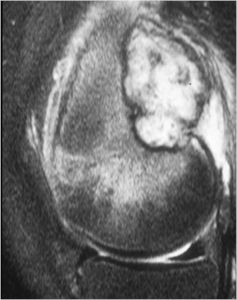

MRI:

- Also useful in determining extent

- There is often extensive edema around the tumor in the surrounding bone and soft tissues that can lead to a misdiagnosis of a malignant tumor.